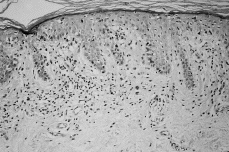

En las fases iniciales de la MF el diagnóstico histológico puede ser difícil. Se caracteriza por un infiltrado linfocitario escaso en dermis papilar, con tendencia a disponerse en banda subepidérmica (Fig. 6). Estos linfocitos presentan epidermotropismo o tendencia a invadir la epidermis. Generalmente aparecen como linfocitos aislados, rodeados de un halo claro, y localizados principalmente en las capas inferiores de la epidermis, con mínima o nula espongiosis; a veces se distribuyen de una manera lineal a lo largo de la unión dermoepidérmica en una disposición como «en fila» (73). La presencia de acúmulos o grupos de linfocitos en la epidermis separados de los queratinocitos adyacentes por un halo claro (microabscesos de Pautrier) es un criterio clásico en el diagnóstico de la MF, pero en las fases iniciales aparece en menos de un tercio aproximado de los casos (74, 75) (Fig. 7).

FIG. 6.--Infiltrado linfocitario ligero en dermis papilar, con tendencia a disponerse en banda.